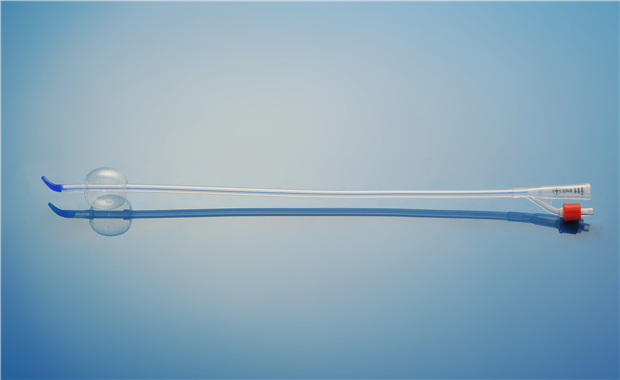

【產品名稱】一次性使用硅膠導尿管 【型號】雙腔彎頭型 【規格】12Fr - 20Fr 【性能�����、主要結構】由醫用硅橡膠為主要原材料制成��,由排泄錐形接口��、球囊充起錐形接口等組成���。